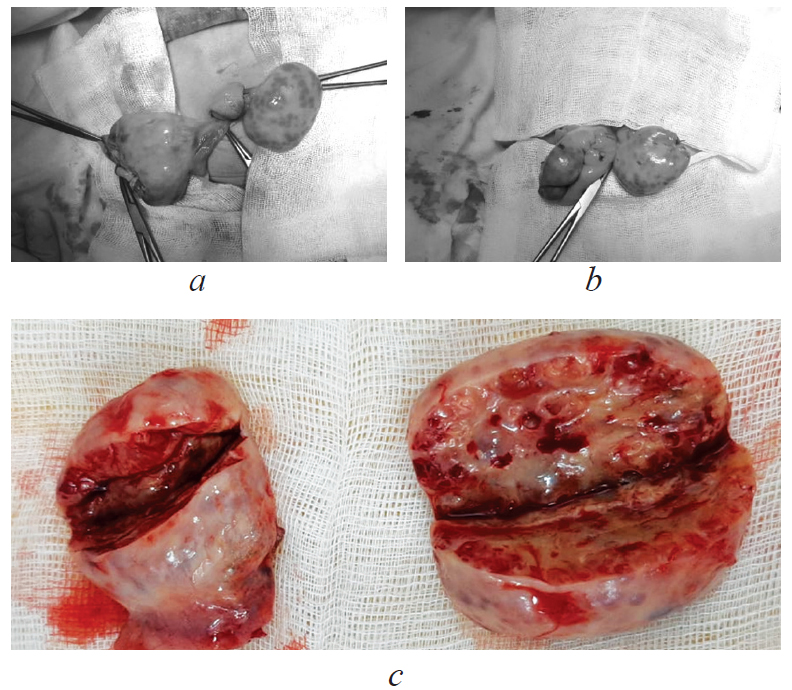

Под эндотрахеальным наркозом в асептических условиях была выполнена супраумбиликальная миниллапоротомия, пункция кисты яичника справа; резекция обоих яичников (рис. 3). Лапароскопическая герниопластика, а также пластика пупочной грыжи.

Рис. 3. Хирургическое лечение: a, b — резекция правого яичника; c — макропрепарат, резецированные яичники

Fig. 3. Surgical treatment: a, b — resection of the right ovary; c — macropreparation, resected ovaries

Размеры яичников: правый 4,4 × 3,5 × 2,5 см, левый 5,2 × 4,5 × 1,5 см. На разрезе в обоих яичниках выявлены множественные кисты размерами максимально 0,5 × 0,4 см. По результатам гистологического исследования определялись множественные фолликулярные кисты, выстланые многорядным фолликулярным эпителием с выраженной пролиферацией клеток и дистрофическими изменениями и явлениями лютеинизации. К фолликулярным кистам широким слоем прилежали крупные тека-клетки. Выявленные морфологические изменения соответствовали вторичному гипертекозу (рис. 4).